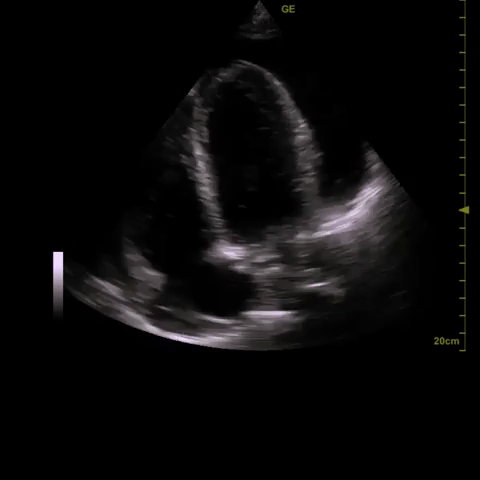

2) ?pericardial effusion (small one noted on initial CT scan)

A diagnostic echocardiogram was performed which was consistent with the POCUS findings. In discussion with Cardiology, a percardiocentesis was performed and over 1L of fluid was aspirated from the pericardial sac (good access from the A4C window). The patient tolerated this well and had a very modest increase in blood pressure following the procedure.